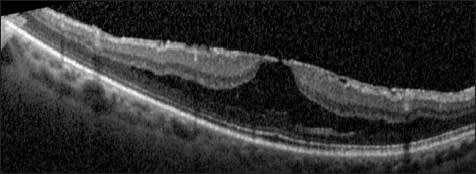

The outer retinal pseudocyst then expands until only a “roof” of retinal tissue is present at the fovea (Figure 4). Finally, the inner retina “roof” opens, and a stage 2 macular hole forms.22, 34, 35 The visualization of adherent posterior hyaloid membrane is aided with OCT. After separation of the posterior hyaloid from the fovea, an operculum or pseudo-operculum may be visualized on OCT.

Figure 4. Foveal pseudocyst. This patient had decreased visual acuity and a yellow foveal ring on examination (stage lB macular hole). A foveal pseudocyst is evident, with a “roof” of tissue covering a nearly full-thickness macular defect. Persistent traction of the posterior hyaloid to the fovea is evident.